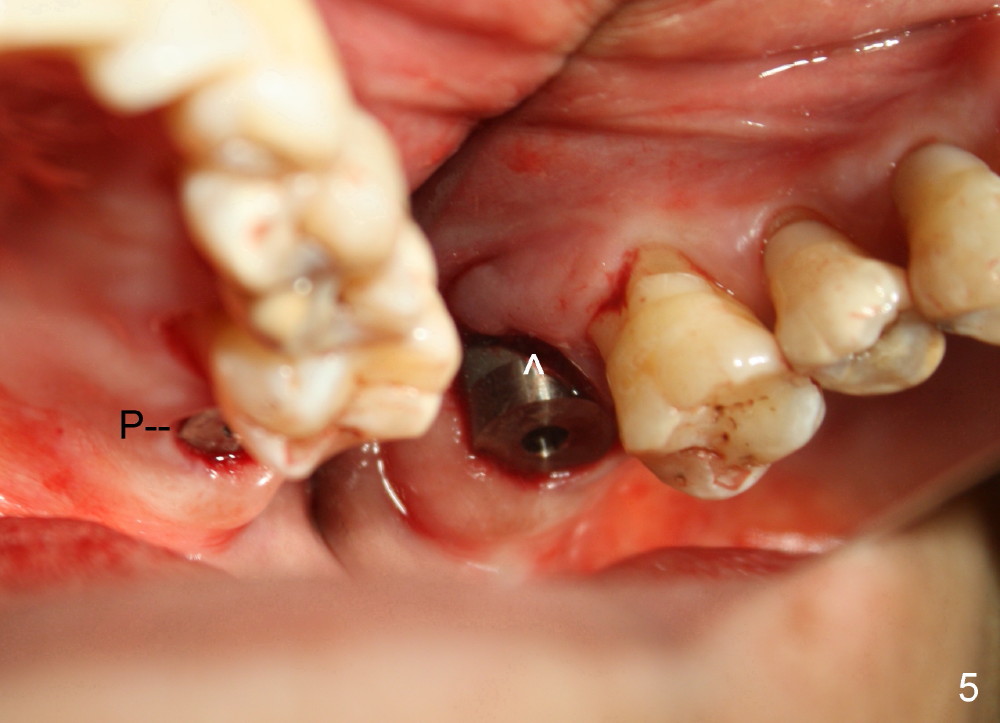

A 56-year-old female has recurrent infection and buccal gingival recession (Fig.1 *) after root canal therapy in the upper left 2nd molar (Fig.2). The extraction socket is single and large. Osteotomy forms by using a series of osteotomes (2-5 mm in diameter) mesiopalatal to the center of the socket. The sinus floor is thin (approximately 2-3 mm). The osteotomy is further enlarged by inserting 4.5-8 mm taps at the depth between 14 and 17 mm from the gingival margin. The last tap has barely achieved stability (Fig.3). It appears that the tap has almost obliterated the socket. Allograft is pushed into the sinus before placement of a 8x17 mm implant. The insertion torque is between 15 and 20 Ncm (Fig.4). The gingiva-level implant is slightly subgingival except buccal (Fig.5). To facilitate buccal gingival re-growth and cover the exposed implant surface, bone graft is placed subgingival (Fig.5 ^). The gingival sulcus is closed partially by placement of a thin strip of collagen membrane (not shown). The wound is protected by applying perio dressing.

Sinus membrane integrity is checked several times intraop: there is no air leakage. There is no nasal hemorrhage or obstruction intra- or post-op. The patient returns for follow up 12 days postop; the perio dressing remains in place (Fig.6).

Next time she returns 4.5 months postop, bone looks normal around the implant (Fig.7), whereas the buccal gingival recession appears to get worse with 1-2 implant thread exposure (Fig.8 >). To avoid this complication, the initial osteotomy should be placed as palatal as possible; when the implant is placed with gingival recession (Fig.5), soft tissue graft should be performed. The implant should be smaller.